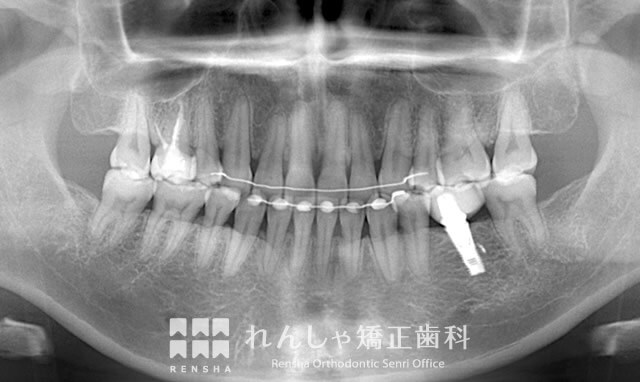

治療経過②

矯正治療による違和感や痛みよりも、歯科矯正用アンカースクリュー埋入時の「音」の方がつらかった

通常、開咬を治すためには、上下の前歯をそれぞれ下方と上方へ引っ張り出す必要があります。同時に、上奥歯を上方へ持ち上げることも重要になります。そのため歯科矯正用アンカースクリューを埋入させてもらいました。

一般的に矯正治療では、装置が当たる違和感や歯を移動させる際の痛みに苦しまれる方が多いもの。しかしC.Nさんによると、この“アンカースクリューの処置の音”が矯正治療中でいちばん嫌だったそう。逆に、矯正自体治療に対する違和感や痛みを訴えられたことはほとんどありませんでした。

治療を進める上で、左下奥歯を抜歯せざるをえなくなったC.Nさん。抜歯した部分には、歯科インプラント治療を受けていただくことに。